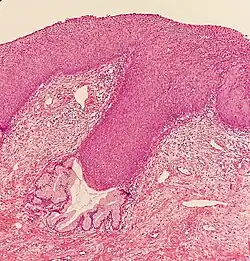

_normal_squamous_epithelium.jpg)

Historically, abnormal changes of cervical epithelial cells were described as mild, moderate, or severe epithelial dysplasia. In 1988 the National Cancer Institute developed "The Bethesda System for Reporting Cervical/Vaginal Cytologic Diagnoses".[12] This system provides a uniform way to describe abnormal epithelial cells and determine specimen quality, thus providing clear guidance for clinical management. These abnormalities were classified as squamous or glandular and then further classified by the stage of dysplasia: atypical cells, mild, moderate, severe, and carcinoma.[13]

CIN is classified in grades:[14]

| Histology Grade | Corresponding Cytology | Description | Image |

|---|---|---|---|

| CIN 1 (Grade I) | Low-grade squamous intraepithelial lesion (LSIL) |

|

| CIN 2/3 | High-grade squamous intraepithelial lesion (HSIL) |

| CIN 2 (Grade II) |

![]() | |

| CIN 3 (Grade III) |

![]() |